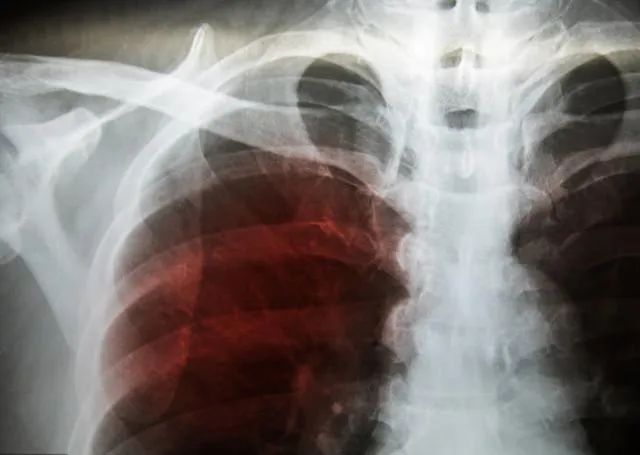

最近收治一个晚期肺腺癌病人,反复发热一周,体温时高时低,最高超过39℃,伴有咳嗽及咳脓痰,在门诊验血提示白细胞、中性粒细胞及C反应蛋白均明显升高,考虑感染性发热,收治住院之后使用广谱抗生素3天,体温降至正常,这时候痰培养结果也出来了,药敏试验提示使用的抗生素对其敏感。

1.感染性发热 这是晚期肺癌病人发热最常见的原因,由于恶性肿瘤阻塞支气管及分支,引起远端肺组织无法通气及排泄痰液,而痰液中的营养物质是细菌最好的培养基,各种细菌在肺内滋生繁殖,从而出现肺部感染。中央型肺癌出现感染性发热的几率高于周围型肺癌,由气道阻塞继发的感染我们称之为阻塞性肺炎。